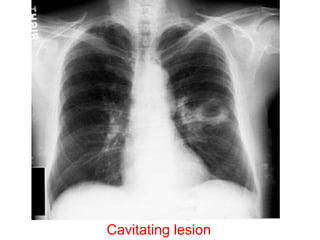

Cavitating lesion